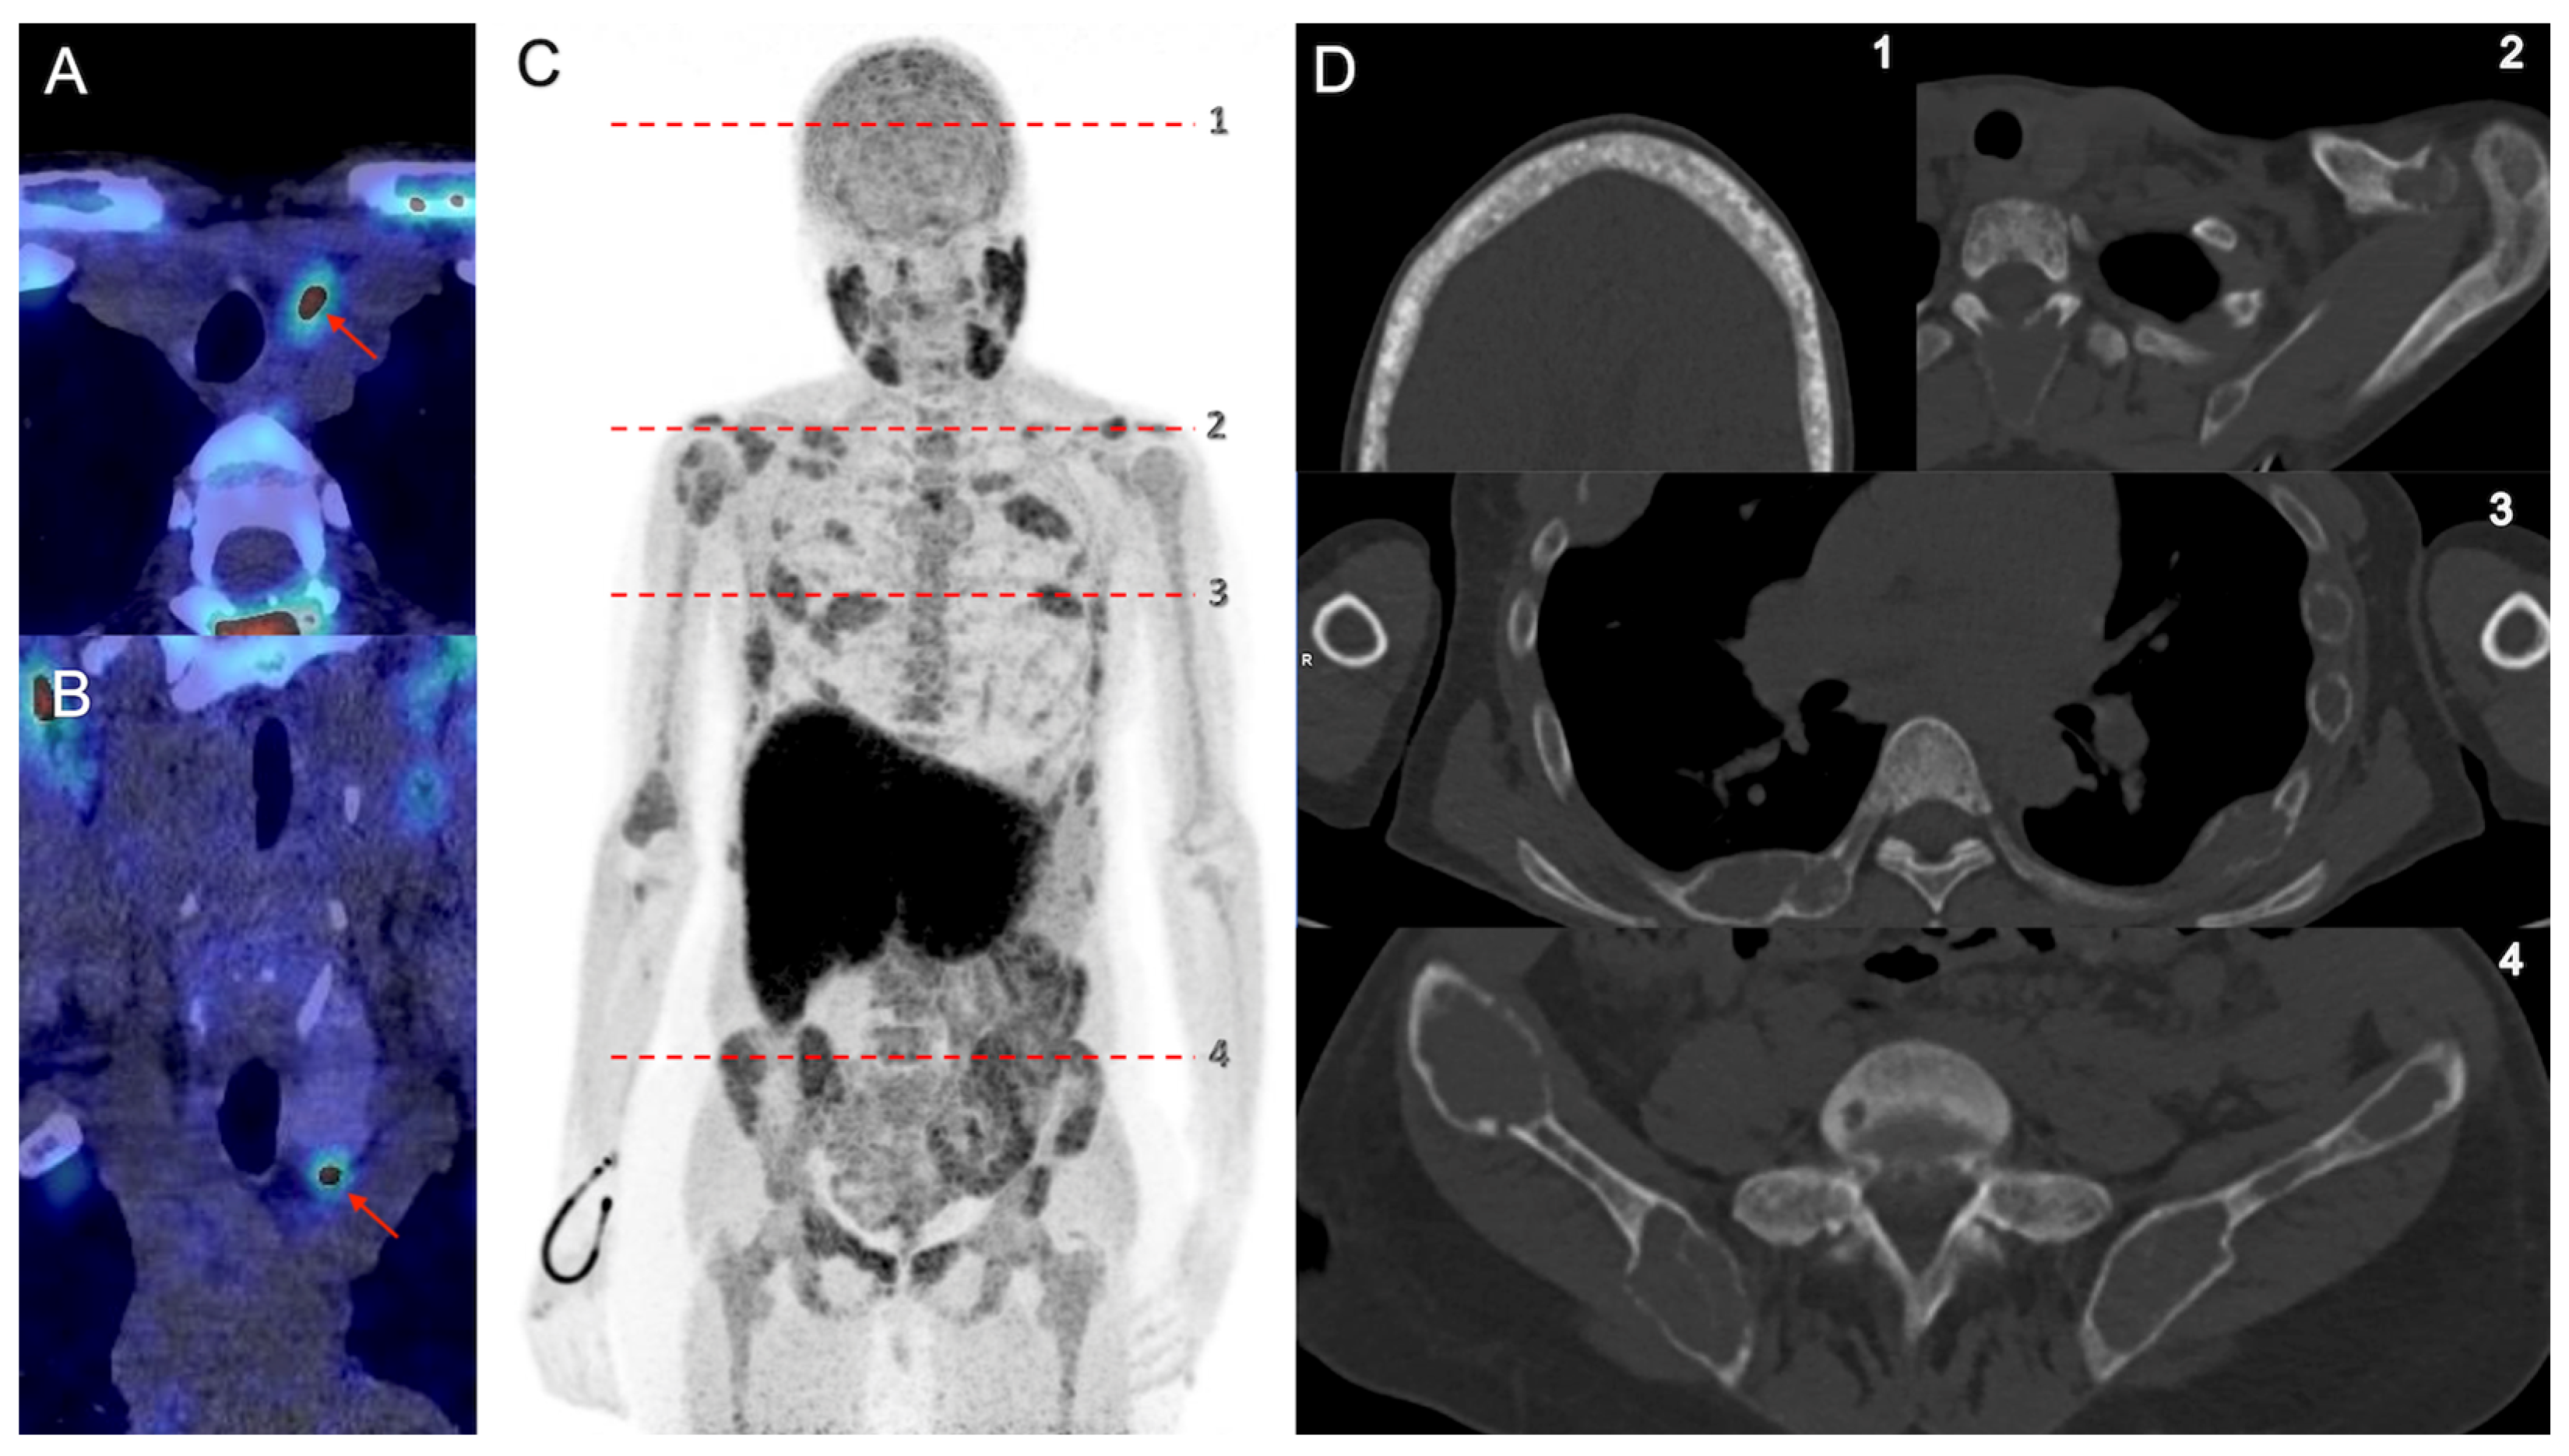

3.2. Parathyroid Imaging